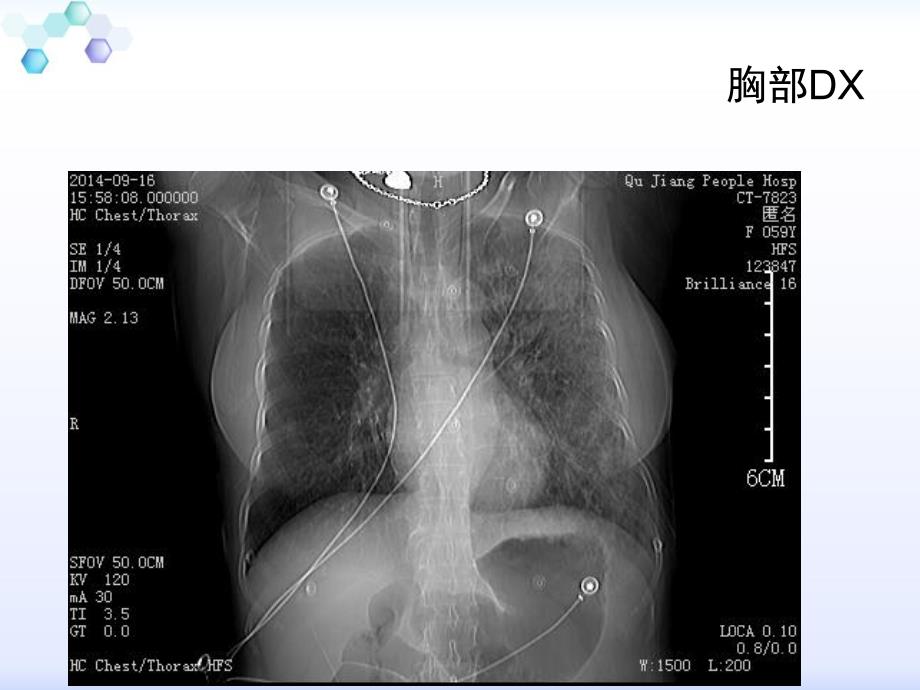

1、恶心呕吐伴寒战咳嗽恶心呕吐伴寒战咳嗽病例分析病例分析病史摘要 患者,女性,56岁,农民,因“恶心呕吐伴寒战,咳嗽3天”于2014-9-16 1:00入住本院急诊科。辅助检查:2014-9-16血常规:白细胞16.61*109/L,中性粒细胞百分比91.4%,血红蛋白124g/L,血小板250109/L,血淀粉酶测定94U/L,CK-MB 28U/L,LDH 344U/L,-羟丁酸脱氢酶283U/L,TNI定性:阴性。腹部立卧位片:腹部上段肠腔积气改变。腹部彩超示:未见明显异常。胸部DX腹部平片 2014-9-16病情变化 2014-9-16 8:20入住病房 入院查体:T:38.7,P:126